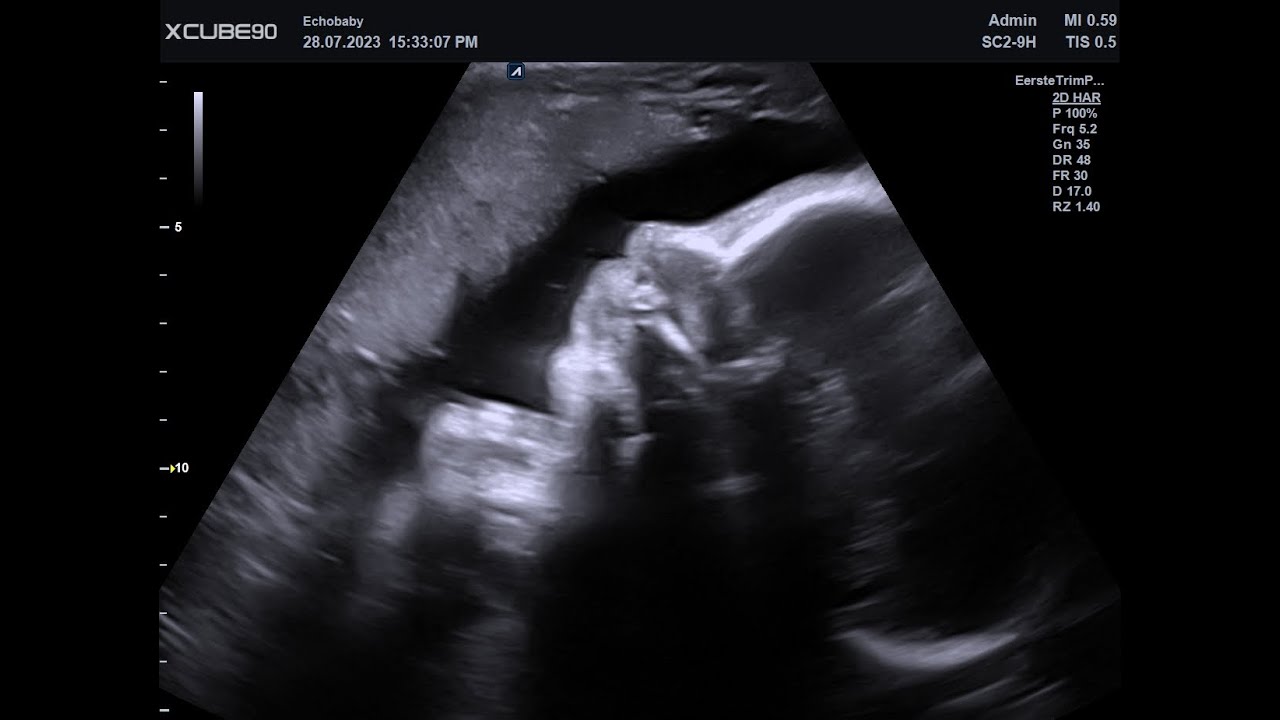

Baby Echo 31 Weken Zwanger Foto's

Baby Echo 31 Weken Zwanger Foto's. Deze echo 31 weken bestaat uit foto's en je ziet er heel wat profieltjes, gewoon omdat dat het mooiste is.  Verder zie je zowel foto's van een jongen als van een meisje en kijk zelf maar verder.